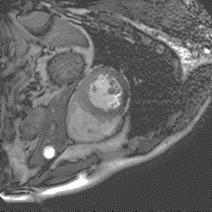

Although supervised deep-learning has achieved promising performance in medical image segmentation, many methods cannot generalize well on unseen data, limiting their real-world applicability. To address this problem, we propose a deep learning-based Bayesian framework, which jointly models image and label statistics, utilizing the domain-irrelevant contour of a medical image for segmentation. Specifically, we first decompose an image into components of contour and basis. Then, we model the expected label as a variable only related to the contour. Finally, we develop a variational Bayesian framework to infer the posterior distributions of these variables, including the contour, the basis, and the label. The framework is implemented with neural networks, thus is referred to as deep Bayesian segmentation. Results on the task of cross-sequence cardiac MRI segmentation show that our method set a new state of the art for model generalizability. Particularly, the BayeSeg model trained with LGE MRI generalized well on T2 images and outperformed other models with great margins, i.e., over 0.47 in terms of average Dice. Our code is available at https://zmiclab.github.io/projects.html.